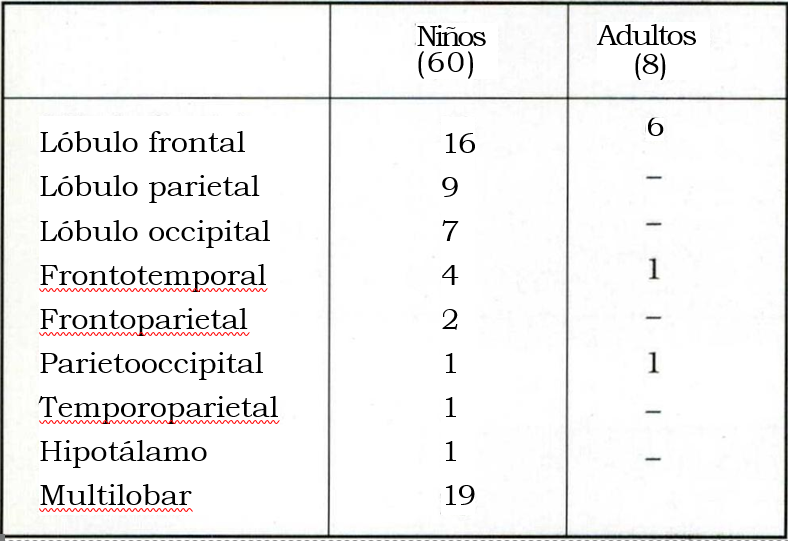

Los exámenes neurológicos realizados se resumen en la tabla 5 y la localización de las lesiones en la tabla 6.

Tabla 6. Localización

En la población pediátrica 19/60 pacientes padecieron epilepsias multilobares, considerando como tales las que involucran 2 o más lóbulos.

Las polectomías y/o lobectomías fueron efectuadas en 8/68 pacientes. El límite posterior de las lobectomías frontales fue el surco precentral. El lateral, 1,5 a 2 cm de la pars opercularis y triangularis del lóbulo frontal, el medial 0,5 a 1 cm de la línea media tratando de respetar la circonvolución supracallosa y la del cíngulo, siempre que no asentara en ellas el área epileptogénica primaria. El limite basal (área frontoorbitaria) lo da la sección del girus recto14. Las resecciones occipitales se efectuaron en pacientes con hemianopsias previas14. La resección del área central y lóbulo parietal efectuada en los niños de hasta 7 años de edad no agregó déficits neurológicos.